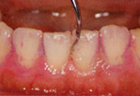

3.洗浄

人によっては歯周ポケット内のバイオフィルムを、歯科医院専用の器具を使って除去(破壊)する必要があります。